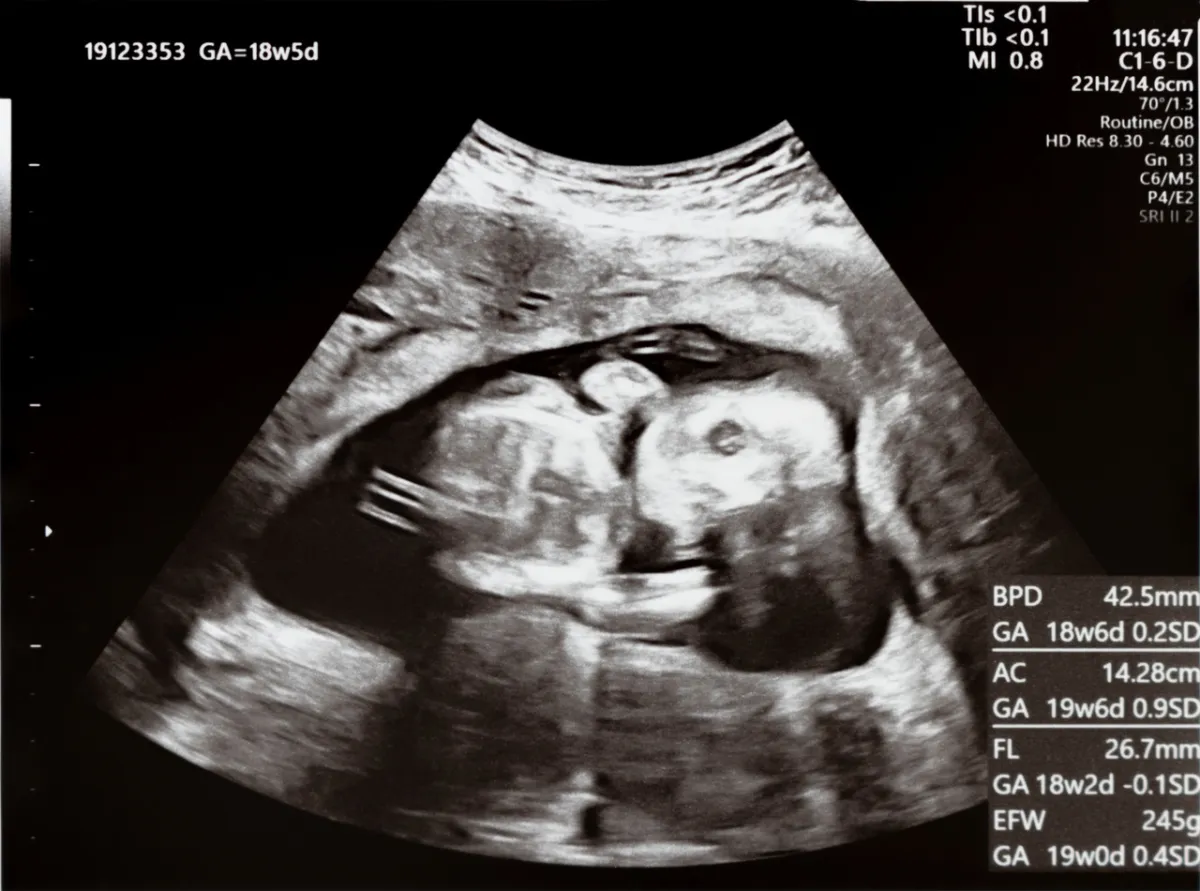

حركة الجنين في الأسبوع 16 إلى 19

من المحتمل أن تلاحظي مشاعر خافتة ورفرفة في رحمك في هذا الوقت تقريباً. إذا كنتِ حاملاً من قبل، فسوف تكونين أكثر دراية بهذا الإحساس وأسرع في التعرف إلى حركات طفلك. وإذا كان هذا هو حملك الأول، فقد يستغرق الأمر وقتاً أطول قليلاً قبل أن تدركي أن تلك الأحاسيس اللطيفة للفقاعات أو الفرقعة، فهي في الواقع حركة طفلك! وقد يكون من الأسهل أن تشعري بطفلك عندما تجلسين بهدوء أو تستلقين.